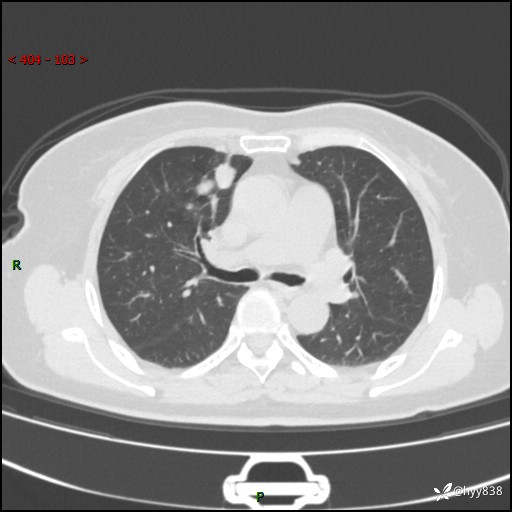

70岁/女,发现右上肺肿物10天。患者过敏体质,只有平扫,错过了一定可惜---结果公布~

【患者信息】:70岁/女

【主诉】:发现右上肺肿物10天

【现病史及既往史】:者10天前因“背部酸痛”于当地治疗,无发热,无呕吐,无头痛头晕等不适,胸部CT示右上肺肿物。遂来我科就诊,门诊看过病人后以“”收入我科, 自患病以来,精神、饮食、睡眠尚可,大小便正常,体力体重无明显减轻。

【检查】:胸部CT平扫(患者过敏体质,不能增强)